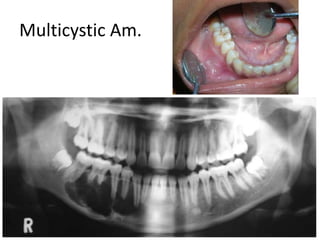

1- Ameloblastoma

Multilocular (Soap bubble> honey comb))

origin (dental lamina and dental organ)

• 40 y (Middle age)

• Males

• Mand. Molar Ramus area

• Sever expansion +Perforation

• Root Resorption

• Teeth Displacement

• Negative aspiration

The shape of the septa

Ameloblastoma

Thick- Coarse & Curved

Well defined in mandible but tend to be ill

defined in maxilla

Multicystic Am.